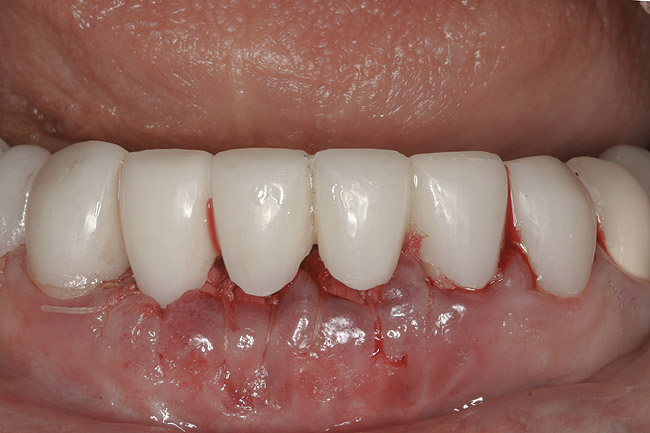

The final treatment plan called for replacement of teeth Nos. 24 through 26 with implants, and four adjacent porcelain crowns. The restorative dentist prepared these four teeth for full coverage and decoronated Nos. 24 and 25, then, with patient input, selected a shade (Figure 3) and fabricated a bis-acryl temporary bridge from Nos. 22 to 28. After extracting teeth Nos. 24 and 25, the periodontist performed socket preservation in addition to horizontal ridge augmentation in site No. 26 with FDBA and a resorbable porcine collagen membrane. The flaps were approximated with 4-0 polyglactin 910 (Figure 4). Figure 5 shows the 7-unit bis-acryl temporary bridge.

Figure 4  Extraction sites Nos. 24 and 25 after socket augmentation; additional grafting, site No. 26; flaps approximated with 4-0 polyglactin 910 sutures.

Figure 4